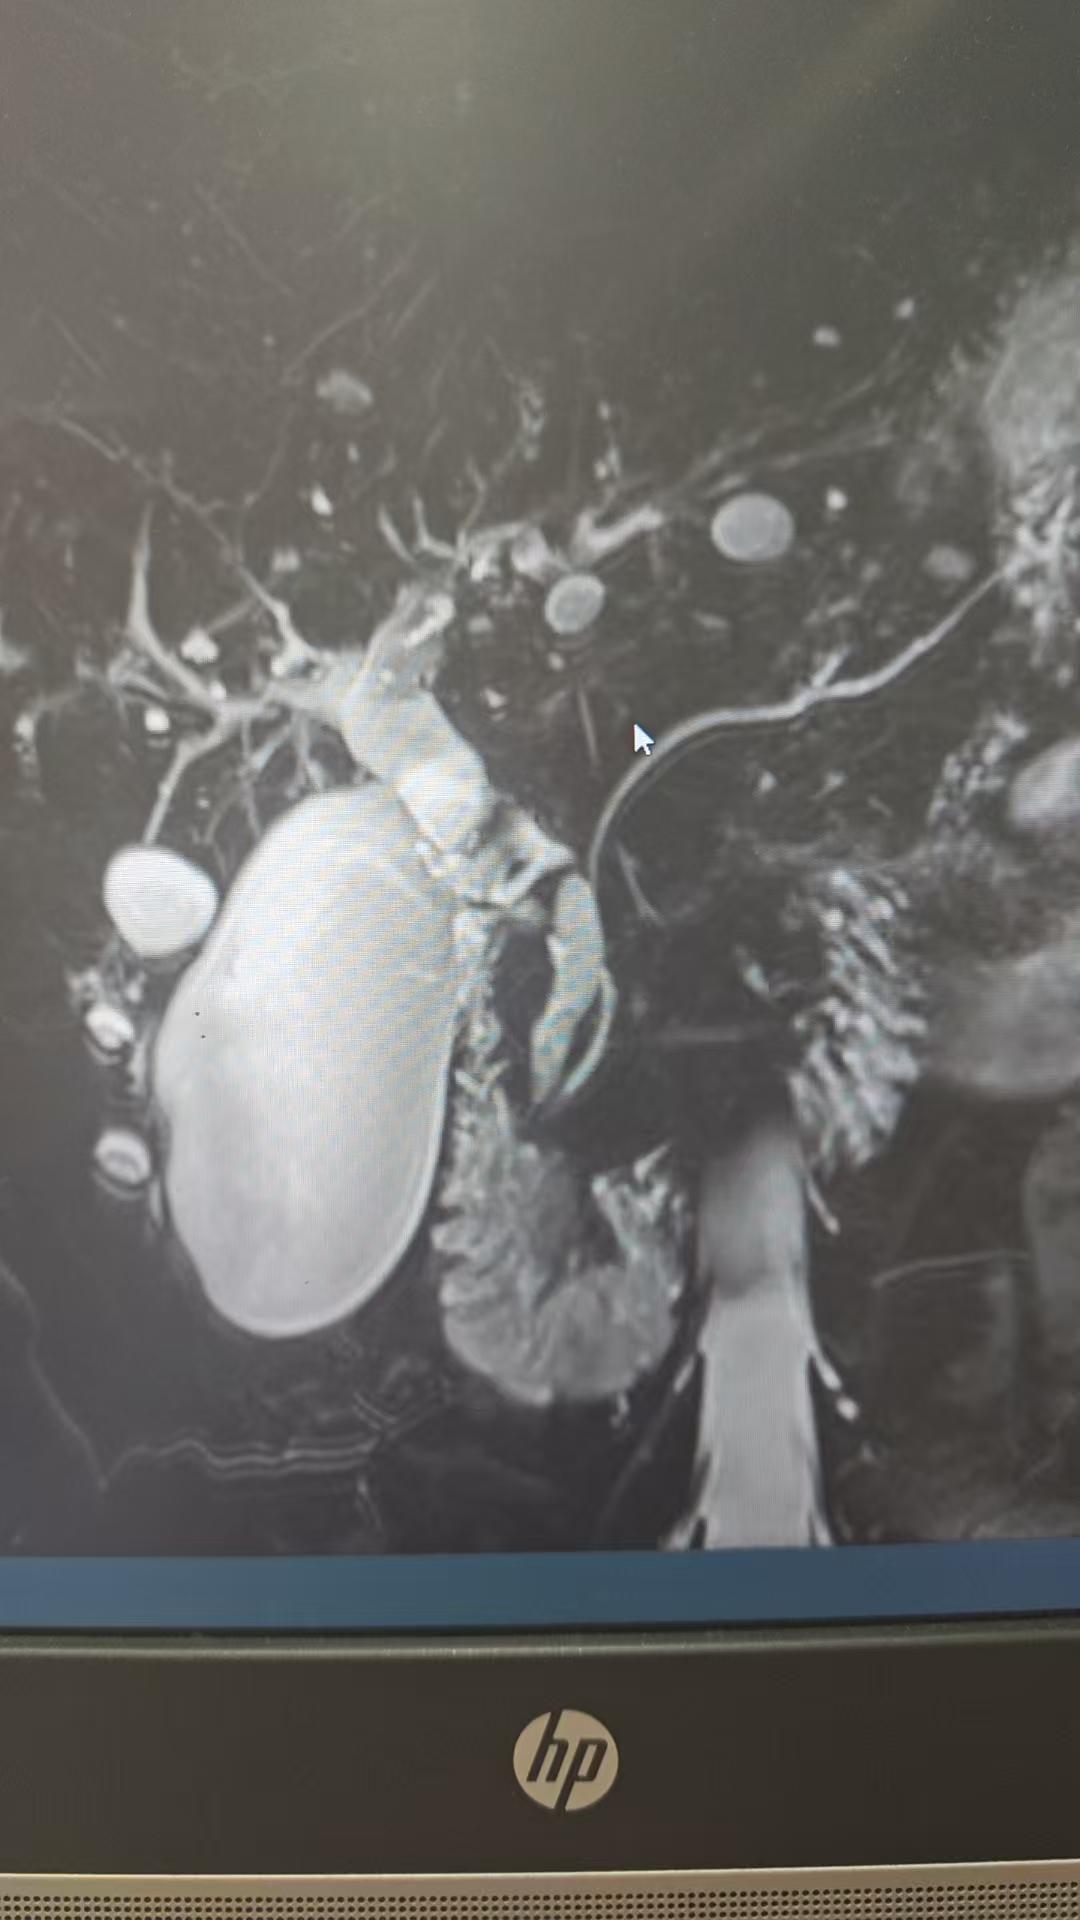

9月21日,洛阳白马医院普外科吕伟子主任团队为73岁高龄患者实施了“腹腔镜联合胆道镜微创手术治疗胆囊结石合并胆总管结石”,一次性微创解决了困扰患者的胆囊结石、胆总管结石及反复发作的胆道炎症等问题。

73岁,高龄患者,因进食油腻食物右上腹疼痛难忍,来到了洛阳白马医院普外科就诊,吕伟子主任随即对患者进行一系列精细的检查,确诊为胆囊结石、胆总管结石,收治入院。

经过充分的术前准备和研究讨论。吕伟子主任带领的普外手术团队决定为患者实施腹腔镜联合胆道镜微创手术治疗胆囊结石合并胆总管结石术。这是一种安全、有效的治疗胆囊结石和胆总管结石的方法,具有创伤小、恢复快、痛苦少等优点。

经紧张而缜密的术前准备后,外科团队为患者施行腹腔镜联合胆道镜微创手术治疗胆囊结石合并胆总管结石术,手术过程顺利,结石被完全清除,术中出血少、创伤小、术后恢复良好,不日即可康复出院。